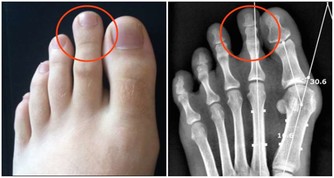

5尿頻、尿少、尿刺痛、四肢腫脹,這說明某些致病因素或毒素過多,影響了腎臟的正常功能